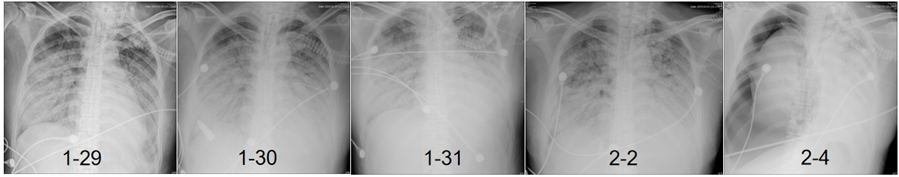

调整方案治疗后,2月2日患者有好转趋势,但在2月4日,由于患者右肺发生气胸(活检在左肺),且出现反复的高危肺栓塞(图8),最终未能抢救成功。